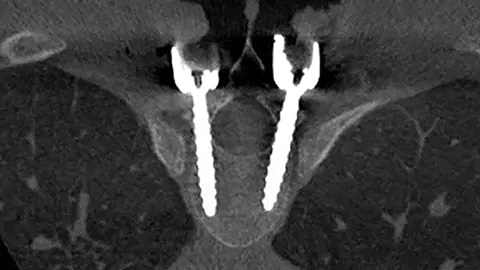

Provides better insights into spinal anatomy to support precise planning and guide effective implant placement.

The Azurion system is the optimal balance between intraoperative image quality and radiation exposure for surgeons and patients."